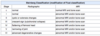

5 variables leading to PE wear characteristics

PE thickness:

- should be >8mm

Articular surface design:

- higher congruity/contact surface area leads to lower contract stress and better wear characteristics

Kinematics:

- ie knee kinematics. Change them to get most congruous implant

PE sterilization:

- Gamma radiation Sterilization in oxygen depleted environment is best

- Then package in vacuum, argon or nitrogen environment

PE machining

- Best is with direct-compression molding